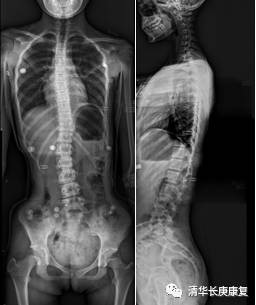

图1初诊X线显示: 脊柱下胸段及腰段有明显的侧弯,侧弯角度约有25°

李女士带着女儿到各大医院看诊,暂无手术指正,目前可进行保守治疗,动态观察脊柱侧弯进展。于是患儿来到我院康复医学科门诊,经过仔细康复评估,配置了个性化的脊柱矫形支具,并在治疗师一对一指导下进行姿势矫正康复训练,经过治疗,患儿脊柱侧弯角度明显减小了,并且其本人不适感也较以前明显缓解。

图2佩戴矫形支具后X线显示:偏移的胸段脊柱较治疗前靠近中线,侧弯角度明显减小。